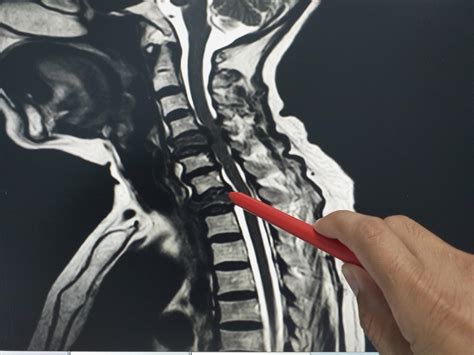

Physicians typically use a combination of physical examinations and advanced imaging to confirm these symptoms. If you report persistent back pain that does not respond to conventional physical therapy, your healthcare provider may suggest the following diagnostic sequence:

• MRI Imaging: The gold standard for visualizing the spinal cord and soft tissue.